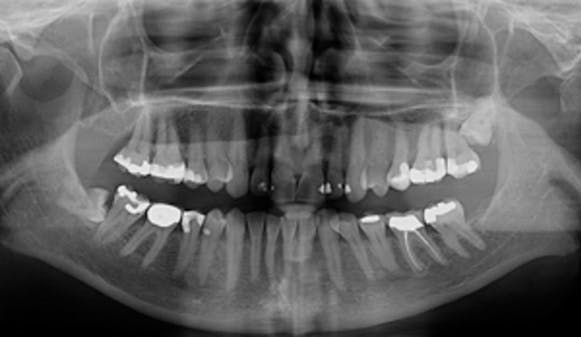

Undersøkelse hos tannlegen

Undersøkelse hos tannlege eller tannpleier bør gjøres årlig, og kan avdekke sykdom i munnhulen…

De fleste forbinder tannlegebesøket med en sjekk etter hull i tennene. En full undersøkelse kan avdekke mye annet...